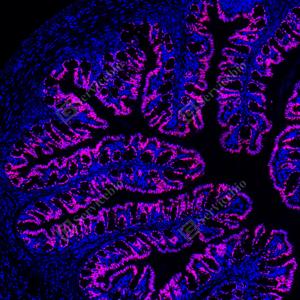

| IF检测CDX2蛋白(货号 GB150083)(红色). 样品: 人结肠癌, 4%多聚甲醛 (货号G1101) 固定12-24小时. 抗原修复: Tris-EDTA抗原修复液(pH 9.0) (G1203), 100℃, 25分钟. 封闭: 3% BSA(货号GC305010)的PBS溶液, 室温孵育30分钟. —抗: 1: 10000稀释, 4℃ 孵育过夜. 二抗: Cy3标记山羊抗兔IgG (H+L) (货号GB21303), 1: 300稀释, 室温孵育1小时. |